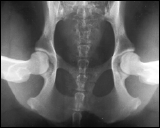

1. Distraktion

Die Hintergliedmaße des Hundes werden in einer neutralen, das Gelenk belastenden Position gelagert. Ein spezielles Instrument wird genutzt, um den angeborenen Spielraum der Hüfte festzustellen. Dieses PennHIP exklusive Verfahren erlaubt eine exakte, reproduzierbare Messung der "Lockerheit" der Hüfte

Distraktions Aufnahme